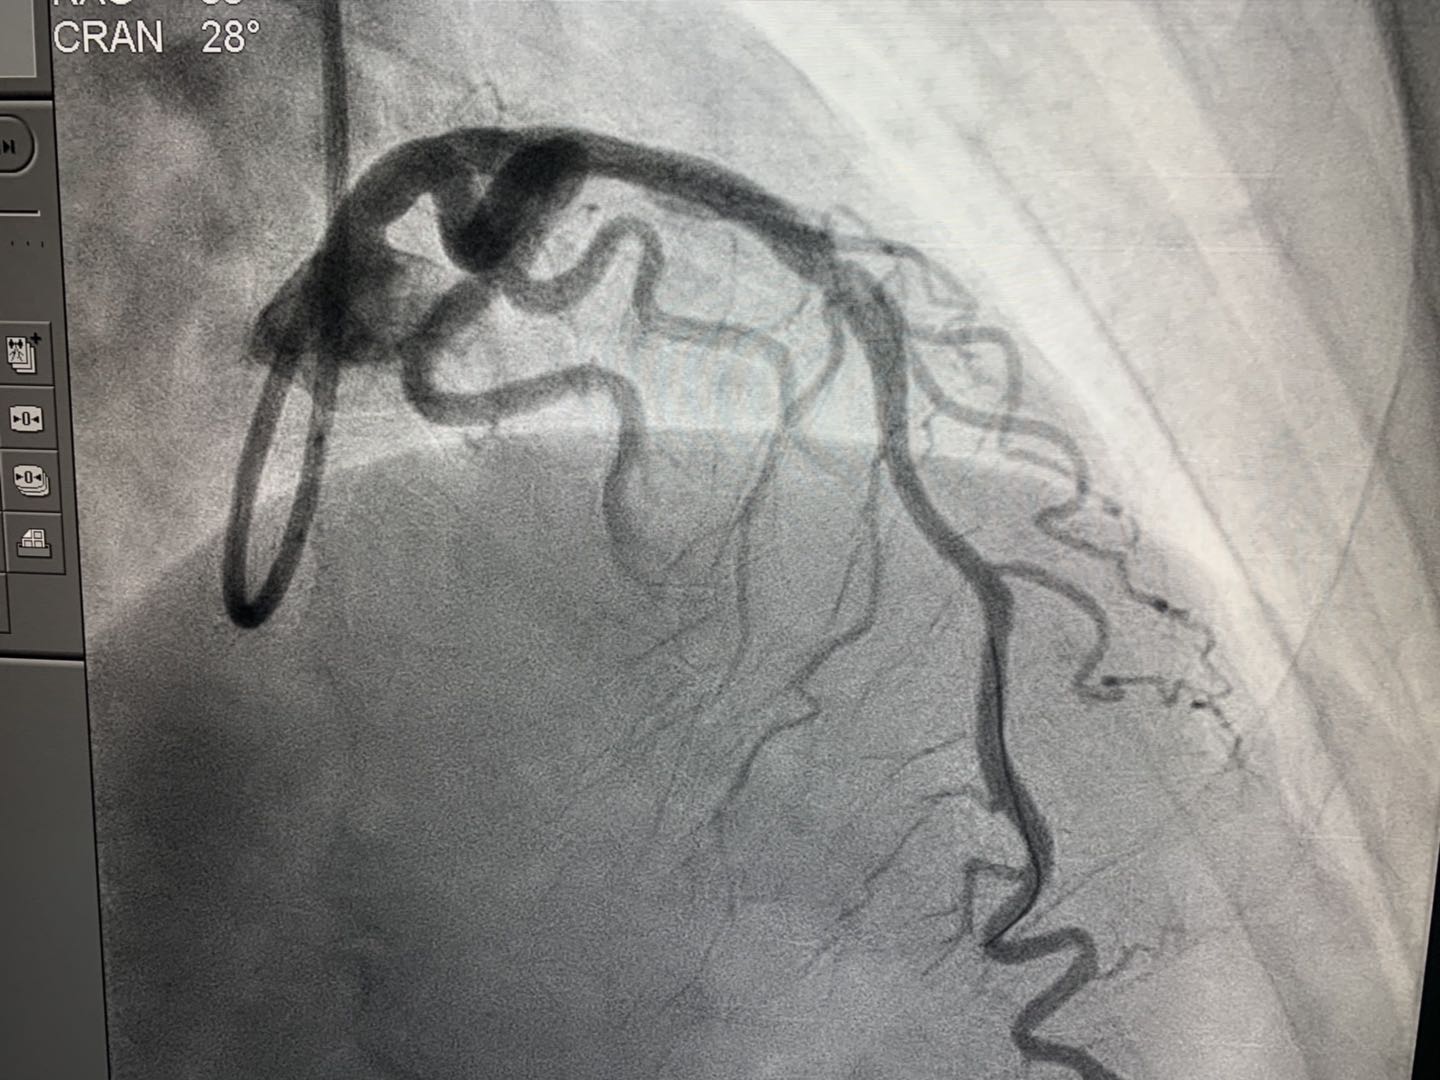

2019年4月16日,新疆首例生物可吸收心脏支架植入术在beat365在线唯一官网附属中医医院(自治区中医医院)成功实施。医院心脏中心冠脉介入团队在武刚主任带领下,为一例50岁男性患者冠状动脉前降支近端成功植入NeoVas生物可吸收支架一枚。术中、术后采用光学相干断层扫描(OCT)对冠脉病变及植入支架进行评估。手术顺利,患者体征平稳。

NeoVas支架,全称为“生物可吸收冠状动脉雷帕霉素洗脱支架系统”,其基体及药物载药涂层分别由可吸收材料制成,支架基体和涂层在体内逐步生物降解和吸收,无永久性支架存患者体内。简单讲,传统支架是金属制成的,一旦进入人体将永久存在,此次使用的可吸收支架是由可降解材料制成,进入人体后会逐渐溶解并消失,不会在体内留下异物,避免了患者受到血管二次堵塞风险。

心内二科武刚主任介绍,心脏支架是心脏介入手术中最常用的医疗器械,具有疏通动脉血管的作用。由于这个“外来物”一旦进入人体后就要终身携带,这也让一些患者特别是年轻的心脏病人产生担忧。冠心病介入治疗(PCI)已经经历了三代技术发展:单纯球囊扩张术、金属裸支架(BMS)和药物洗脱支架(DES)。生物可吸收支架是冠脉支架的发展方向,可解决药物洗脱金属支架永久异物的痛点。目前世界范围内应用的支架大部分是第三代支架——药物洗脱支架,由于其材质为金属的,植入后会在人体内永久存留金属异物。

武刚主任医疗团队此次植入可吸收支架的材料为聚乳酸等,在植入体内后2-3年可完全降解,而且可以恢复血管的功能和弹性,不会永久存留,所以被认为是冠心病治疗的第四次革命。同时对于金属支架过敏的冠心病患者是个很好的选择。预计未来可吸收支架会被广泛使用,冠心病介入治疗将进入新的时代。(介入治疗室魏玲)